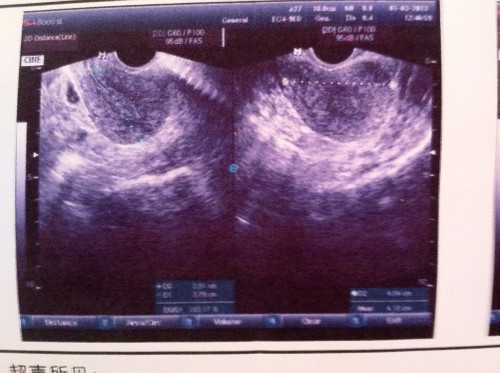

随着现在人们生活水平的提高,每餐都是离不开大鱼大肉的,现在走在路上看到10个人都有两个是胖子,3个是偏胖的人群,去医院看病B超提示多囊,大部分人会很紧张不能怀孕怎么办,焦虑,医生就会说10个人里面有1个人就是多囊,不用吃药,不用手术,先回去减肥吧,听到这里还是需要一探究竟怎么回事,减肥了就可以怀孕了吗?现在的不孕不育还是存在很多的,多囊表现在哪里?